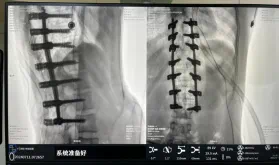

據悉脊柱側彎手術治療后可以保持軀干平衡,改善外觀并防止畸形進一步發展?;颊叩纳钯|量得到提高,進而減少脊柱過度畸形可能帶來的疾病的發生率,外觀上的積極變化往往也能帶來患者心理與精神的積極變化。臨床上會綜合考慮患者的年齡、側彎程度、進展趨勢、骨質條件、鄰近節段情況、手術節段等因素,合理采用個性化的手術方式進行治療。然而,由于脊柱神經血管密布,手術操作相對復雜,手術難度高、風險大,傳統脊柱側彎的手術方式往往有較高的神經或脊髓損傷風險。故此次科室決定開展機器人輔助導航下脊柱側彎矯形、植骨融合內固定手術。術前,醫生團隊在機器人多維度圖像融合智能手術規劃功能的輔助下,預先規劃了理想的置釘路徑。術中,天璣骨科手術機器人準確遵循術前規劃,根據配準結果,實時定位并準確執行置釘操作,所有導針均用電鉆置入,一次性成功,協助醫生順利完成手術。最終,在麻醉科、手術室密切配合下,歷時3小時成功完成側彎矯形術,出血量僅500ml。術后,患者恢復良好,大小便及下肢神經運動感覺正常。

圖為置釘后

此次在充分保證患者安全和手術效果的前提下使用機器人輔助下手術的成功實施,大大降低了高難度手術的風險,并進一步減輕了患者手術創傷、縮短了康復時間。這也標志著南方醫院贛州醫院脊柱外科治療個性化、精準化、智能化水平進一步提升。